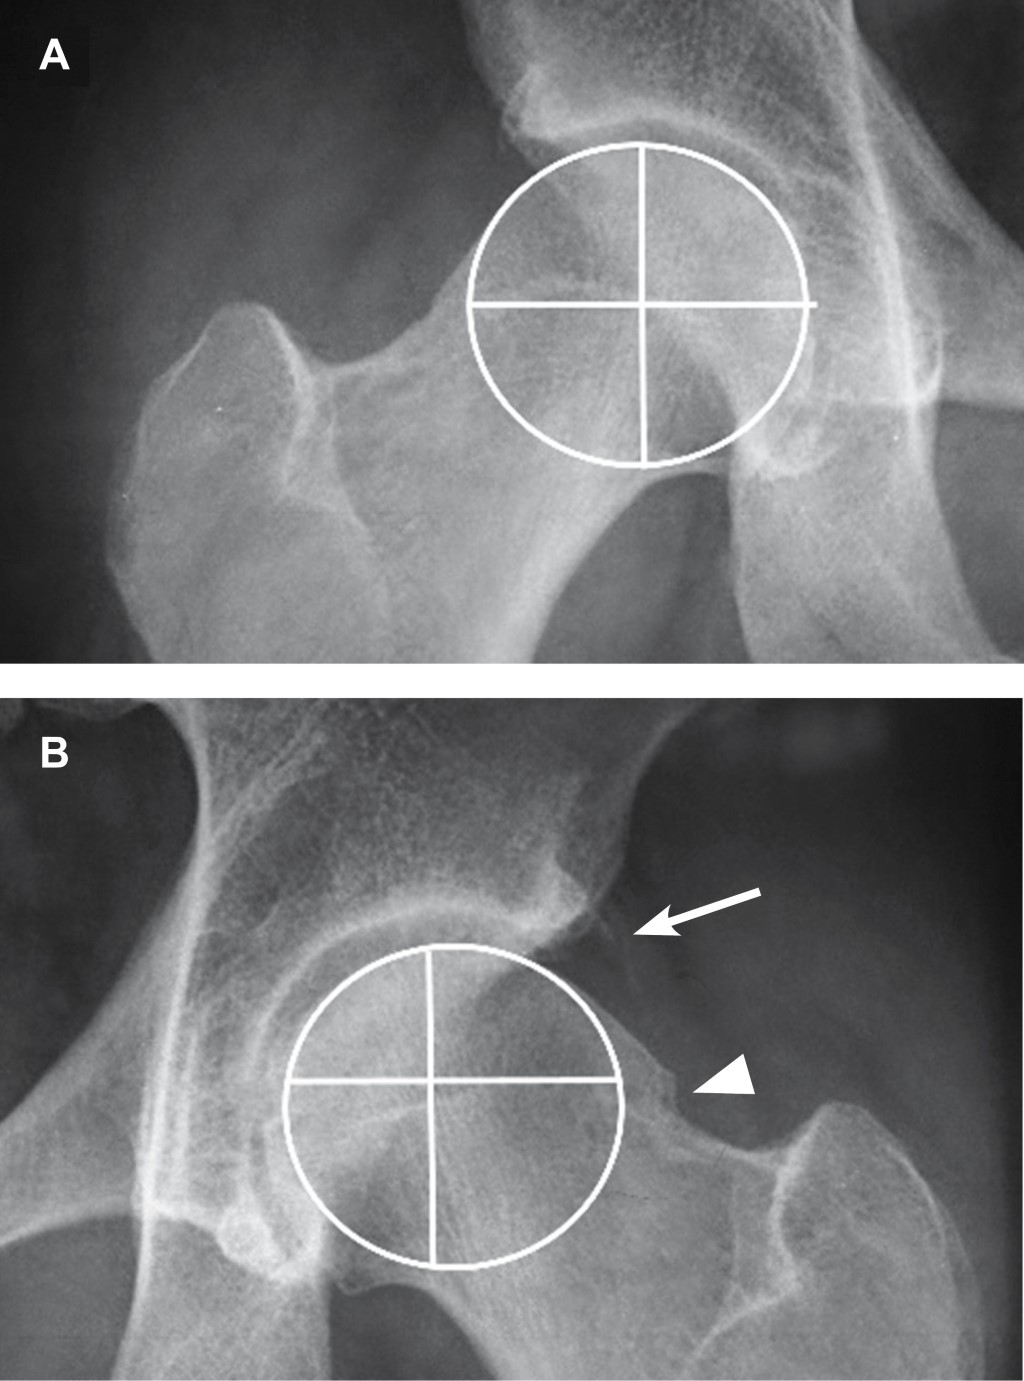

Masculino de 36 años de edad, profesionista, sin antecedentes de importancia, con dolor inguinal de un año de evolución, que se exacerba posterior a juego de balompié, obligándolo a suspender la actividad. A la exploración dirigida, postura y marcha sin alteraciones, dolor a la exploración de articulación coxofemoral durante la rotación interna y aducción con flexión de cadera a 90o, al igual que durante abducción con cadera en posición neutra. En radiografía anteroposterior de cadera se observa anormalidad de fémur izquierdo en la unión cabeza cuello, correspondiendo a pinzamiento femoroacetabular tipo leva (Figuras 1, 2 y 3).

El pinzamiento femoroacetabular tipo leva (FAI tipo CAM por sus siglas en inglés) (la leva es un elemento mecánico que está sujeto a un eje en un punto que es excéntrico a su centro geométrico) es una causa conocida de dolor inguinal que puede provocar osteoartritis de la cadera. Los pacientes que padecen esta afección son principalmente jóvenes que experimentan dolor inguinal durante los movimientos de rotación interna y aducción con la articulación coxofemoral en flexión de 90o; ocasionado por contacto anormal entre la unión cabeza-cuello femoral y el borde acetabular debido a anormalidad anatómica del fémur, ya que la morfología de la cabeza femoral no es esférica por alteración o anomalía del cuello femoral.1 Esta anormalidad se observa en 40% de los pacientes que desarrollan osteoartritis de cadera; puede ser secundaria a enfermedades del fémur proximal típicas de la infancia, incluidas secuelas de epifisiolistesis de la cabeza femoral, enfermedad de Legg-Calvé-Perthes, a infección de la articulación coxofemoral en la infancia y traumatismos de la articulación. Al ser una patología dinámica su desarrollo también está relacionado con actividad deportiva intensa. La prevalencia de la deformidad del choque femoroacetabular tipo leva es mayor en el género masculino.2 Su diagnóstico temprano resulta importante para establecer estrategias de tratamiento en pacientes con dolor de cadera preartrítico, la serie radiográfica de cadera al igual que la resonancia magnética y la tomografía con medición del ángulo alfa proporcionan las pautas de medición prequirúrgica.3 El pinzamiento femoroacetabular se puede tratar mediante procedimiento quirúrgico abierto o por artroscopia. Se informan complicaciones clínicamente relevantes en 4.8% de los pacientes con cirugía abierta y la tasa general de complicaciones asociadas con la artroscopia de cadera es discretamente menor (4%).4

Figura 3